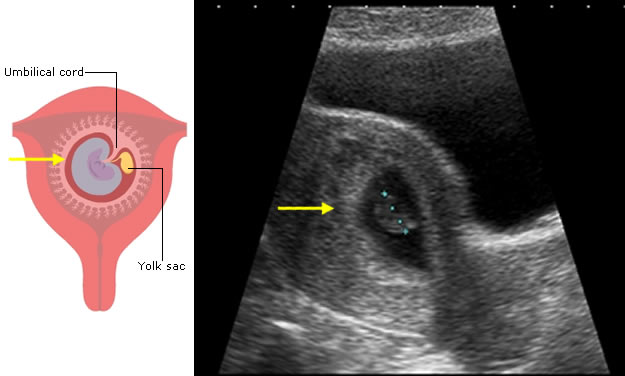

The first feature to be seen on ultrasound is the gestation sac, which will become the amniotic and chorionic sacs. These contain fluid and are seen as black on ultrasound.

The trophoblast is specially modified embryonic tissue which allows the pregnancy to implant into the uterine wall. It is almost white on ultrasound and part of it will form the placenta.

The embryo itself is usually only seen after 6 weeks following the last period.

Note: in this ultrasound image of an early pregnancy, the sonographer has made a measurement of the length of the developing baby (dotted blue line). You will learn about this measurement later in this session.